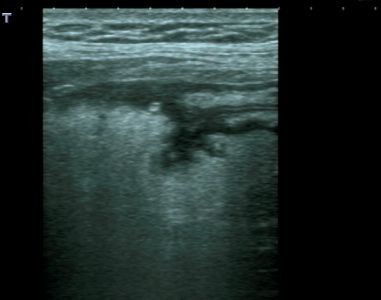

Lo studio medico privato del Dottor Patrizio Stornelli è ad Avezzano è dotato di un'attrezzatura ecografica moderna. Oltre alla ecografia addominale dei parenchimi, si esegue l'ecografia gastroenterolgica ed in particolare l'ecografia del tenue, che consente la diagnosi ed il follow-up particolaremente dei paziente con malattia di Crohn, ma anche l'ecografia del colon. Grazie a questo approccio è possibile scansionare interi segmenti del colon con particolare riguardo alla patologia diverticolare ma anche di indiduare l'appendice e di porre diagnosi di certezza di eventuale appendicite acuta.